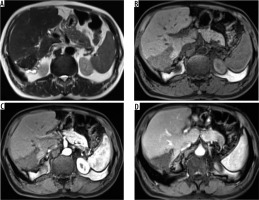

On non-contrast CT, 15 patients (65%) revealed hypodense hepatic mass with scattered foci of calcification with no associated cystic component (Figures 1 and 2). Four (17.3%) patients revealed complex hepatic mass with hypoattenuating cystic areas and hyperattenuating calcifications (Figure 3). Four (17.3%) patients revealed thick walled hypodense cystic lesion (Figure 4). None of the lesions showed intralesional enhancement in arterial, portal, or hepatic venous phase CT (Figures 1 and 2). Five cases showed mild peripheral irregular enhancement in hepatic venous phase. Hepatic atrophy with capsular retraction was seen in three cases. One patient had superadded infection with hepatic abscess formation that required pigtail catheter drainage. With regards to the extent of disease, seven patients showed peripheral hepatic lesions with no biliary or vascular involvement (P1). Biliary radical obstruction was seen in seven patients. Peripheral biliary radicals above the primary confluence were infiltrated in four (P2). Hepatic hilar involvement with both lobe biliary radical dilatation was seen in three patients (P3). Single hepatic vein involvement was seen in three patients (P2). Three patients showed combined infiltration of at least two hepatic veins (P3). Main portal vein encasement was seen in two patients, and two showed combined infiltration of both IVC and hepatic veins (P4) (Figure 5). Extra hepatic infiltration was seen in four cases including adrenal gland infiltration in two patients, parietal wall infiltration in one patient, and diaphragmatic invasion in one patient (Figure 6) (N1 disease). Three patients showed metastatic disease. Two among them had pulmonary involvement (Figure 6) and one had splenic involvement (M1 disease). A break up of the patients according to PNM staging is given in Table 2. On MRI all the patients showed hypointense signal intensity on T1-weighted sequence. On T2-weighted sequence one (5.2%) patient showed micro-vesicular cysts with no solid component (Kodama type 1) (Figure 3C). Six (31.5%) patients showed heterogeneous signal intensity mass with both hypointense solid and hyperintense cystic components (Kodama type 2) (Figure 3D). Two (10.5%) patients showed central hyperintense cystic component with surrounding hypointense solid component (Kodama type 3). Eight (42.1%) patients showed hypointense mass with no cystic component (Kodama type 4) (Figure 7). Two patients (10.5%) showed thick walled cystic lesions (Kodama type 5) (Table 3). Post-contrast T1-weighted images revealed no enhancement of the lesion. Three cases showed peripheral rim of enhancement in delayed phase. DWI revealed free diffusion characterised by low signal intensity on high b value DWI images and high signal on ADC in all cases (Figure 8) except one patient who had developed superadded infection with abscess formation and required pigtail drainage. Mean ADC value of HAE was 1.74 ± 0.48 × 10-3 mm2/s (range: 1.39 × 10-3 mm2/s to 2.3 × 10-3 mm2/s). Mean ADC of different Kodama types of HAE did not differ significantly from each other (p = 0.058) (Table 3). The mean ADC of the surrounding liver parenchyma was 1.10 ± 0.21 × 10-3 mm2/s.

Figure 7

T2-weighted axial (A) and corresponding T-weighted magnetic magnetic resonance (MR) image (B) reveals solid hypointense peripheral lesion in segment VII. Post-contrast volumetric interpolated breath-hold examination (VIBE) MR image in arterial (C) and portal venous phase (D) reveals absence of contrast enhancement